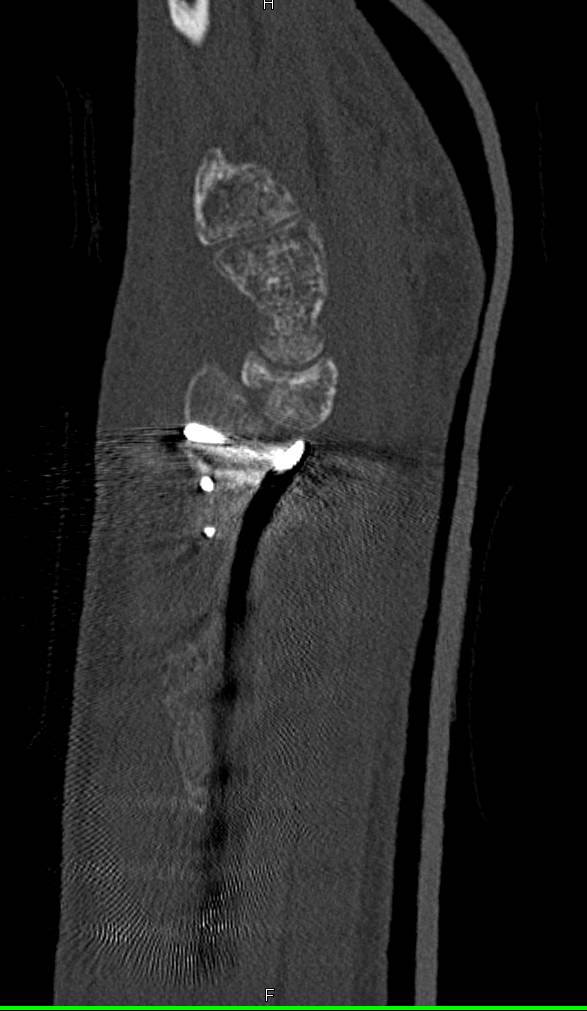

Bony Deformity with Remodelng of Tibia